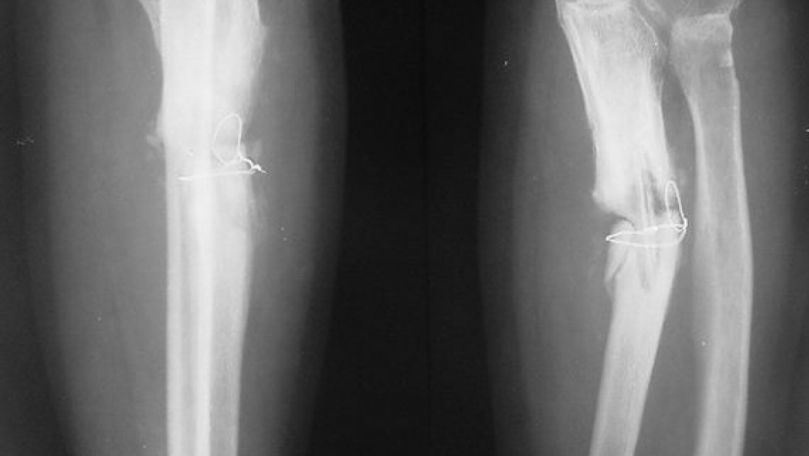

Adezivul are o rezistență ridicată și este complet biodegradabil, fiind absorbit de organism odată cu vindecarea oaselor. Această inovație reduce nevoia de intervenții chirurgicale complicate, evitând implanturile metalice și scurtând timpul de recuperare al pacienților.

Testele clinice au arătat rezultate promițătoare, inclusiv în cazuri unde fracturile ar fi fost dificil de tratat prin metode clasice. Tehnologia are un potențial ridicat pentru utilizare în spitale, în situații de urgență sau în intervenții minim invazive.